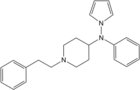

Pyrrole-fentanyl [36] | N-[1-(2-Phenylethyl)piperidin-4-yl]-N-pyrrol-1-ylpropanamide | |

|